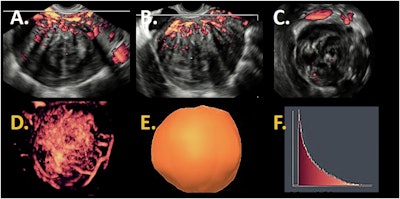

3D power Doppler images of the same patient. Sagittal view (A), transversal view (B), and coronal view (C). 3D power Doppler reconstruction (D) with a 3D power Doppler volume (E) and a histogram (F) as output of 3D power Doppler ultrasound with vascular indices as result.